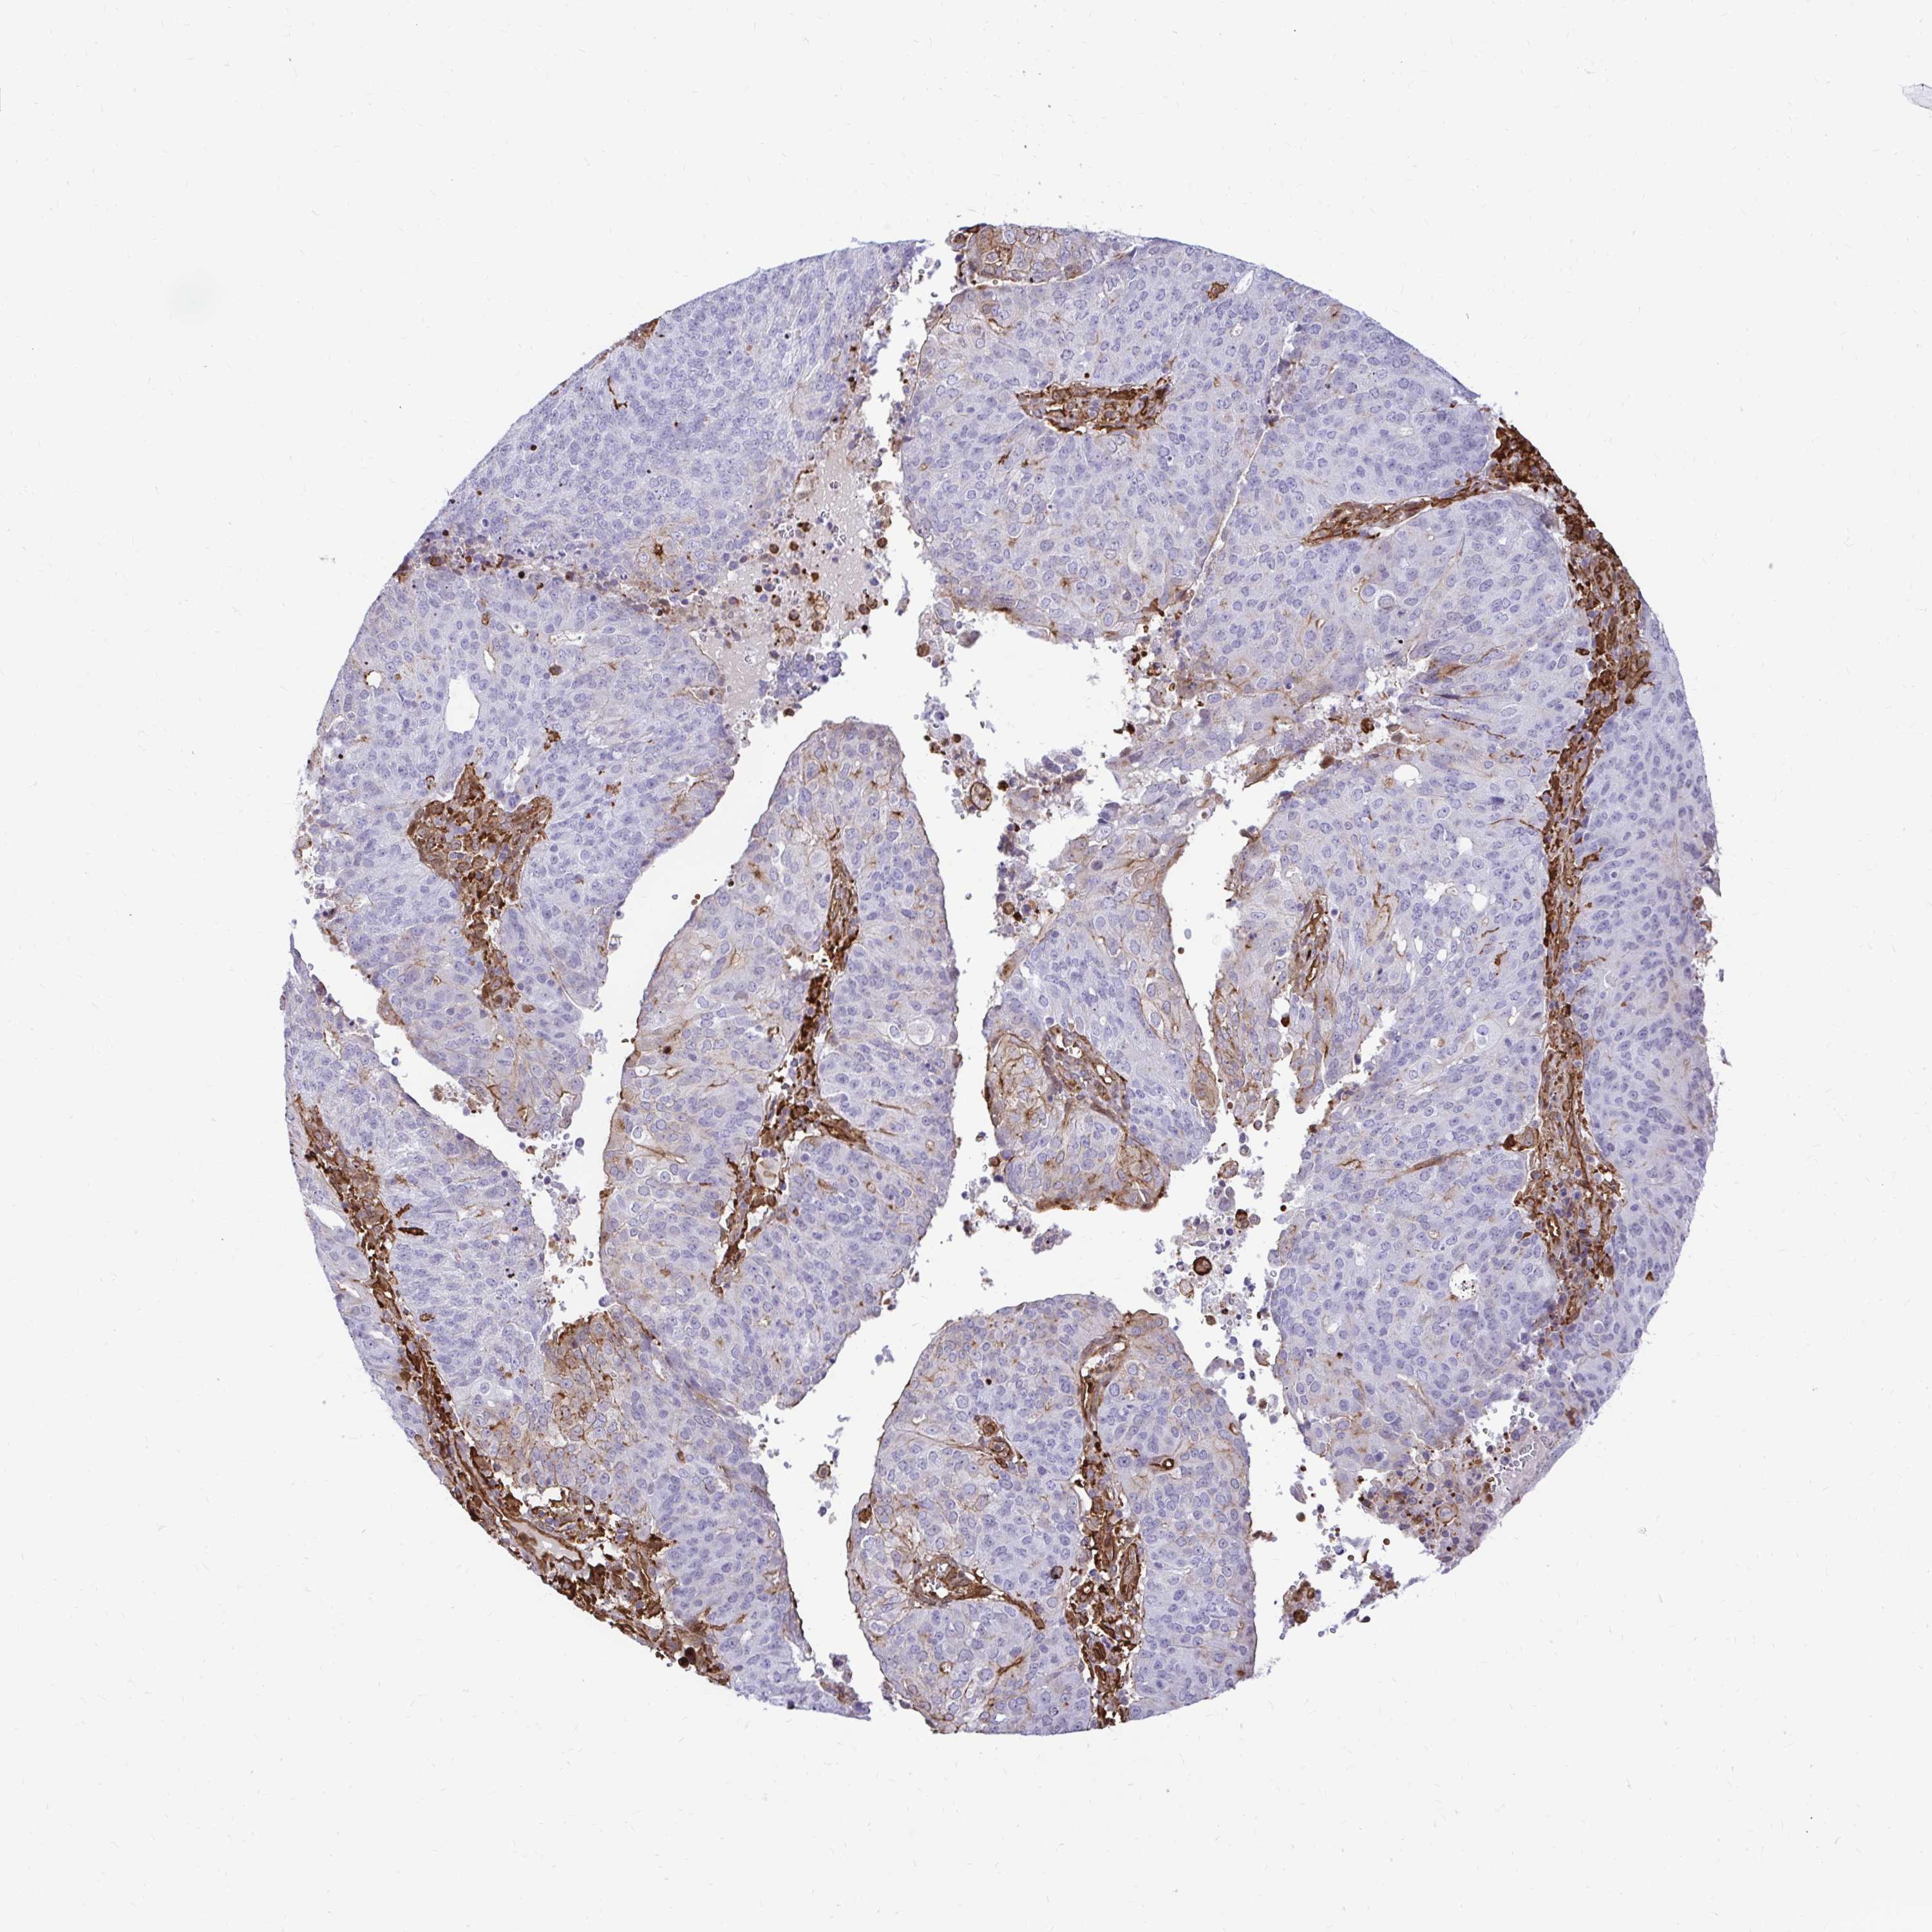

ENDOMETRIAL CANCER - Protein expressioni

A mouse-over function shows sample information and annotation data. Click on an image to view it in a full screen mode. Samples can be filtered based on level of antibody staining by selecting one or several of the following categories: high, medium, low and not detected. The assay and annotation is described here.

Note that samples used for immunohistochemistry by the Human Protein Atlas do not correspond to samples in the TCGA dataset.

Antibody stainingi

Antibody staining in the annotated cell types in the current human tissue is reported as not detected, low, medium, or high, based on conventional immunohistochemistry profiling in selected tissues. This score is based on the combination of the staining intensity and fraction of stained cells.

Each image is clickable and will lead to virtual microscopy that enables deeper exploration of all samples and also displays staining intensity scores, fraction scores and subcellular localization as well as patient and tissue information for each sample.

Antibody HPA054026

Antibody CAB010823

Antibody CAB016728

Antibody CAB036009

Staining

High

Medium

Low

Not detected

Intensity

Strong

Moderate

Weak

Negative

Quantity

>75%

75%-25%

<25%

None

Location

Nuclear

Cytoplasmic/membranous

Cytoplasmic/membranous,nuclear

Adenocarcinoma, NOS

Adenocarcinoma, metastatic, NOS